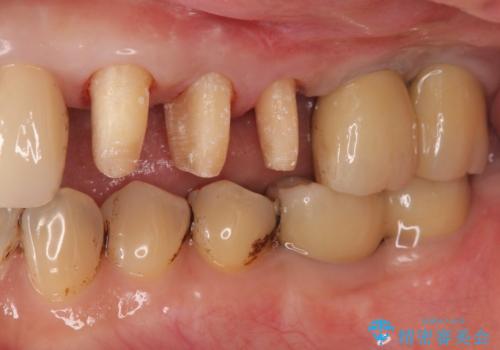

- 夜間のくいしばり、はぎしりが激しく全体的な歯周病が進行し、治療を希望され来院されました。

歯周ポケットの徹底的な除去を行なったのち、歯の揺れを抑え、過大な力がかからぬよう連結クラウン(歯周補綴)を行い強大な力に対抗します。

- 55万円(仮歯×3・ファイバーコア×3・歯周外科)費用は治療当時の料金となります